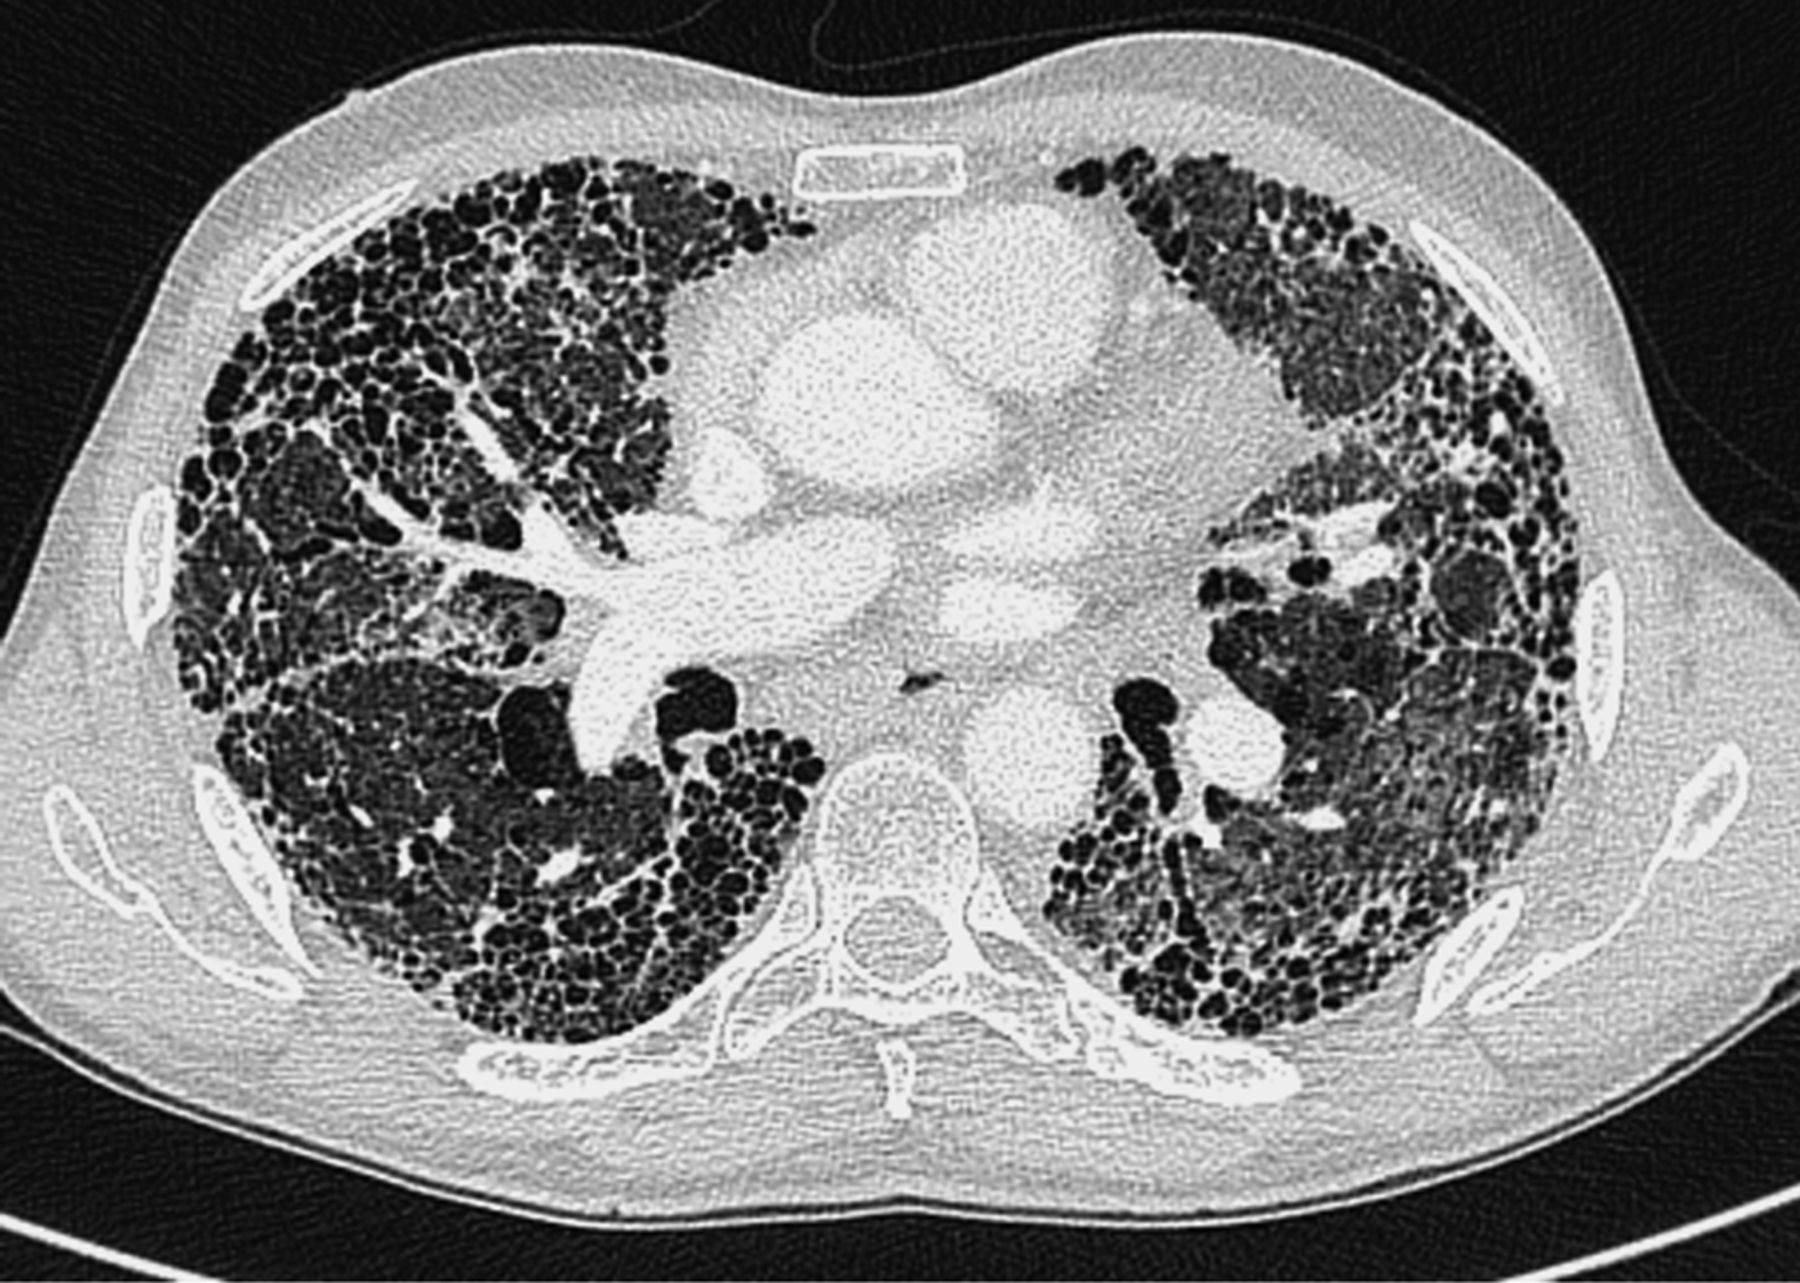

肺纤维化是以成纤维细胞增殖及大量细胞外基质聚集并伴炎症损伤、组织结构破坏为特征的一大类肺疾病的终末期改变,也就是正常的肺泡组织被损坏后经过异常修复导致结构异常(疤痕形成)。绝大部分肺纤维化病人病因不明(特发性),这组疾病称为特发性间质性肺炎(IIP),是间质性肺病中一大类。而特发性间质性肺炎(IIP)中最常见的以肺纤维化病变为主要表现形式的疾病类型为特发性肺更多>>